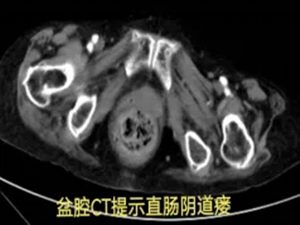

在积极止血过程中,团队发现出血并非单纯的直肠肛门问题,怀疑可能合并阴道瘘。初步处理后,患者被转入胃肠甲状腺外科进一步诊治,最终确诊为直肠阴道瘘并局部感染出血。

然而,真正的挑战才刚刚开始:患者20多年前曾接受直肠肿瘤手术,此次手术方案的制定难度陡增。高龄、既往直肠癌手术史、阴道瘘感染、凶猛的出血——其中任何一项单独出现,都已属高危;此刻,却全部叠加在一起。

杨战锋主任建议启动"疑难病例云平台",共商手术预案。经北上广深多位专家线上会诊,最终探讨出最佳治疗方案。手术顺利完成后,患者平安度过危险期。